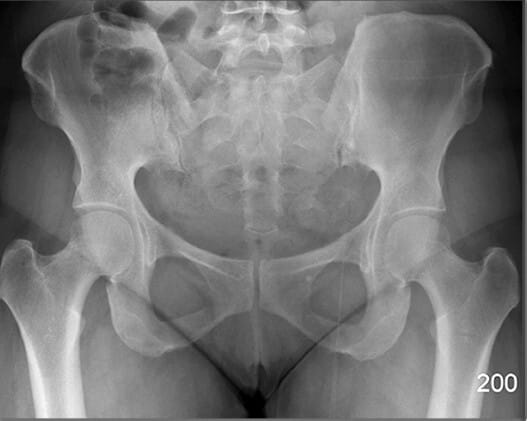

Bony Structures (AP View)

Pelvic Region

PELVIS